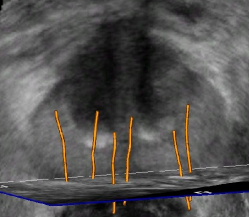

The framework was validated on 278 registrations of 295 US volumes from 17 patients. The 17 reference images were acquired shortly before the intervention, and the tracking images were acquired after a biopsy shot. The clinical protocol was approved by the ethical committee of the XXX hospital, Town, Country, and all patients consented to participate to the study. The images were acquired with a GE Voluson and a RIC5-9 endorectal US probe. The algorithms were executed on a 4-core 2.6Ghz processor. In order to provide a reference gold standard for the evaluation of registration accuracy, experts manually segmented 467 point fiducials that were clearly identifiable on multiple images (e.g. calcifications and cysts). The distances between fiducial pairs were measured after registration to estimate the local accuracy. Note that the unavoidable segmentation error increases the measured error in average; this approach hence underestimates accuracy. Accuracy was computed for all registrations that were qualified as valid by experts after visual inspection, which represent 97,8 of the registrations. The results for both rigid and elastic registration are given in Tab. 1, and a visual illustration of the registration performance is given in Fig. 2. Fig. 3 shows 3D biopsy maps created with our biopsy tracking system.

Biopsy tracking systems potentially add significant clinical value to prostate cancer diagnosis and therapy planning. Immediate advantages are the possibility to avoid resampling of already biopsied tissues when repeating a biopsy series, interventional quality control of the biopsy distribution (e.g. detection of unsampled areas) and computer-assisted guidance to non-systematic targets. The latter could for example be identified on MR/spectroMR images of the gland. Moreover, the improved knowledge about the biopsy and thus the cancer position could be used to implement focal therapy strategies for prostate cancer. 3D US based elastic tracking can provide the precision required for such therapeutic applications.